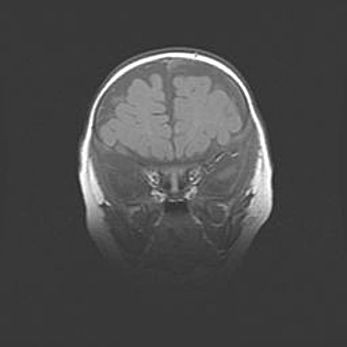

Церебральная ишемия II.

Возраст: 5 дней

Вес: 3400 г

Пол: женский

Окружность головы: 35 см

Срок гестации: 39 недель

Церебральная ишемия – это заболевание, характеризующееся недостаточностью (гипоксией) либо полным прекращением (аноксией) снабжения мозга кислородом по причине закупорки одного или нескольких сосудов. Это приводит к  что метаболическим расстройствам различной степени тяжести в тканях головного мозга, развитию коагуляционных некрозов и гибели нейронов.